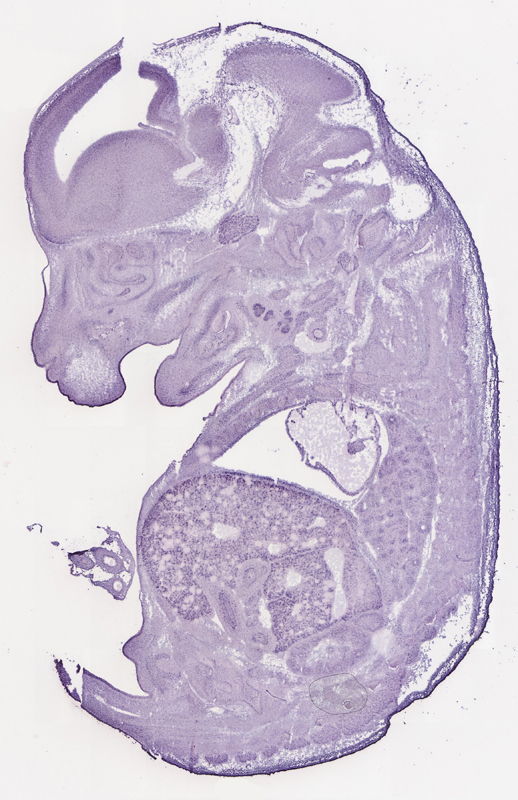

Specimen

euxassay_003443_16:

embryonic day 14.5

euxassay_003443_17: